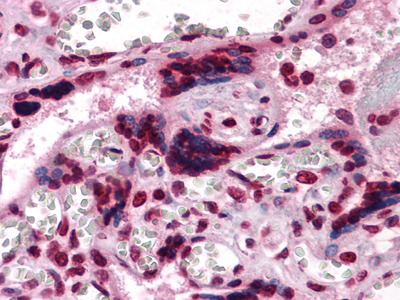

ELISA, Immunofluorescence, Immunohistochemistry, Western Blot

ELISA, IF (Immunofluorescence), IHC (Immunohistochemistry), WB (Western Blot)

The M-CSF csf1 (Catalog #AAA320151) is an Antibody produced from Mouse and is intended for research purposes only. The product is available for immediate purchase. The M-CSF Monoclonal Antibody reacts with Human and may cross-react with other species as described in the data sheet. AAA Biotech's M-CSF can be used in a range of immunoassay formats including, but not limited to, ELISA, IF (Immunofluorescence), IHC (Immunohistochemistry), WB (Western Blot). Researchers should empirically determine the suitability of the M-CSF csf1 for an application not listed in the data sheet. Researchers commonly develop new applications and it is an integral, important part of the investigative research process. It is sometimes possible for the material contained within the vial of "M-CSF, Monoclonal Antibody" to become dispersed throughout the inside of the vial, particularly around the seal of said vial, during shipment and storage. We always suggest centrifuging these vials to consolidate all of the liquid away from the lid and to the bottom of the vial prior to opening. Please be advised that certain products may require dry ice for shipping and that, if this is the case, an additional dry ice fee may also be required.Precautions